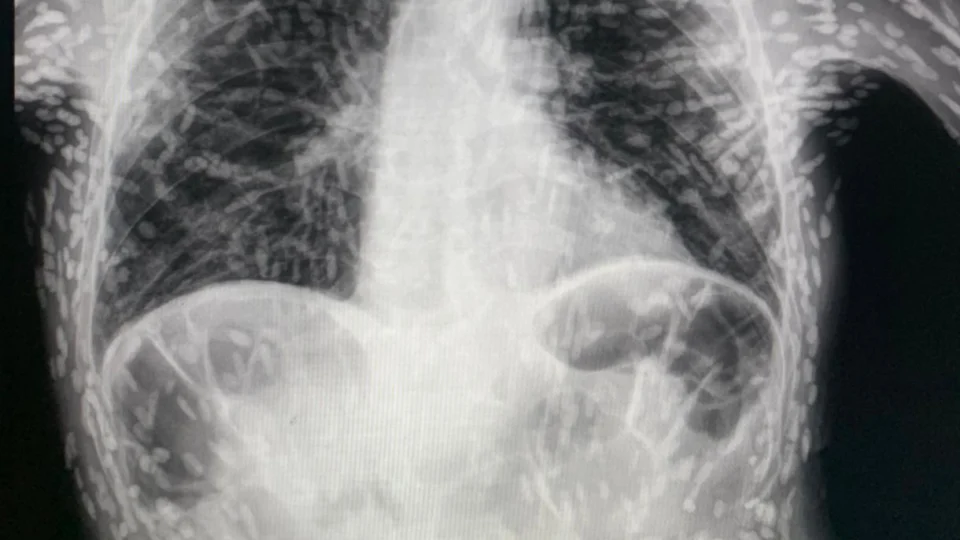

Médico divulga raio-x de paciente com tórax cheio de ‘ovos de verme’

O médico Vitor Borin de Souza compartilhou a radiografia do tórax de um paciente com doença parasitária, cheio de ovos de verme, no último domingo (16), em São Paulo.

No exame de imagem é possível ver os ovos de tênia pelo corpo do paciente, diagnosticado com um quadro de cisticercose.

Conforme o médico, residente pelo Hospital das Clínicas de Botucatu (SP), a doença é adquirida a partir da ingestão do ovo da tênia.

Ainda segundo o especialista, a transmissão acontece através de fezes humanas, de portadores do parasita.

O médico acrescenta que a doença não é ocasionada por carne mal cozida e sim, por vegetais contaminados, sem lavagem.

Vitor Borin sinalizou aos internautas, preocupados com o estado do paciente, que os ovos de tênia encontrados já estavam mortos.

O médico informou que, não identificada lesão na cabeça, medula e olhos, não há necessidade de tratamento.

Vitor Borin explicou que os vermes calcificados estão inviáveis, inativos.

No caso do paciente do raio-x, o médico comunicou que o paciente solicitou o exame após apresentar 2 meses de tosse.